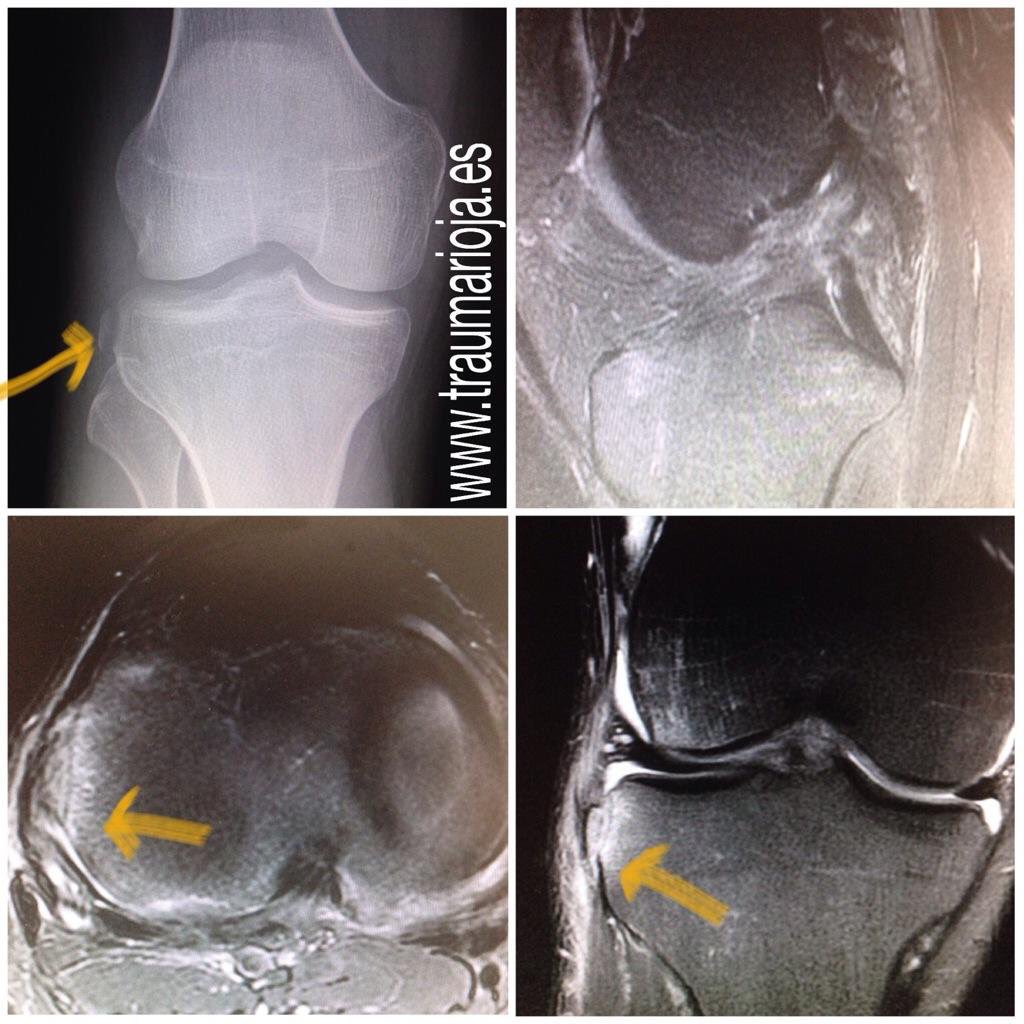

"Fractura de Segond" signe patognomònic de trencament del LCA. Inserció tibial de lligament anterolateral.